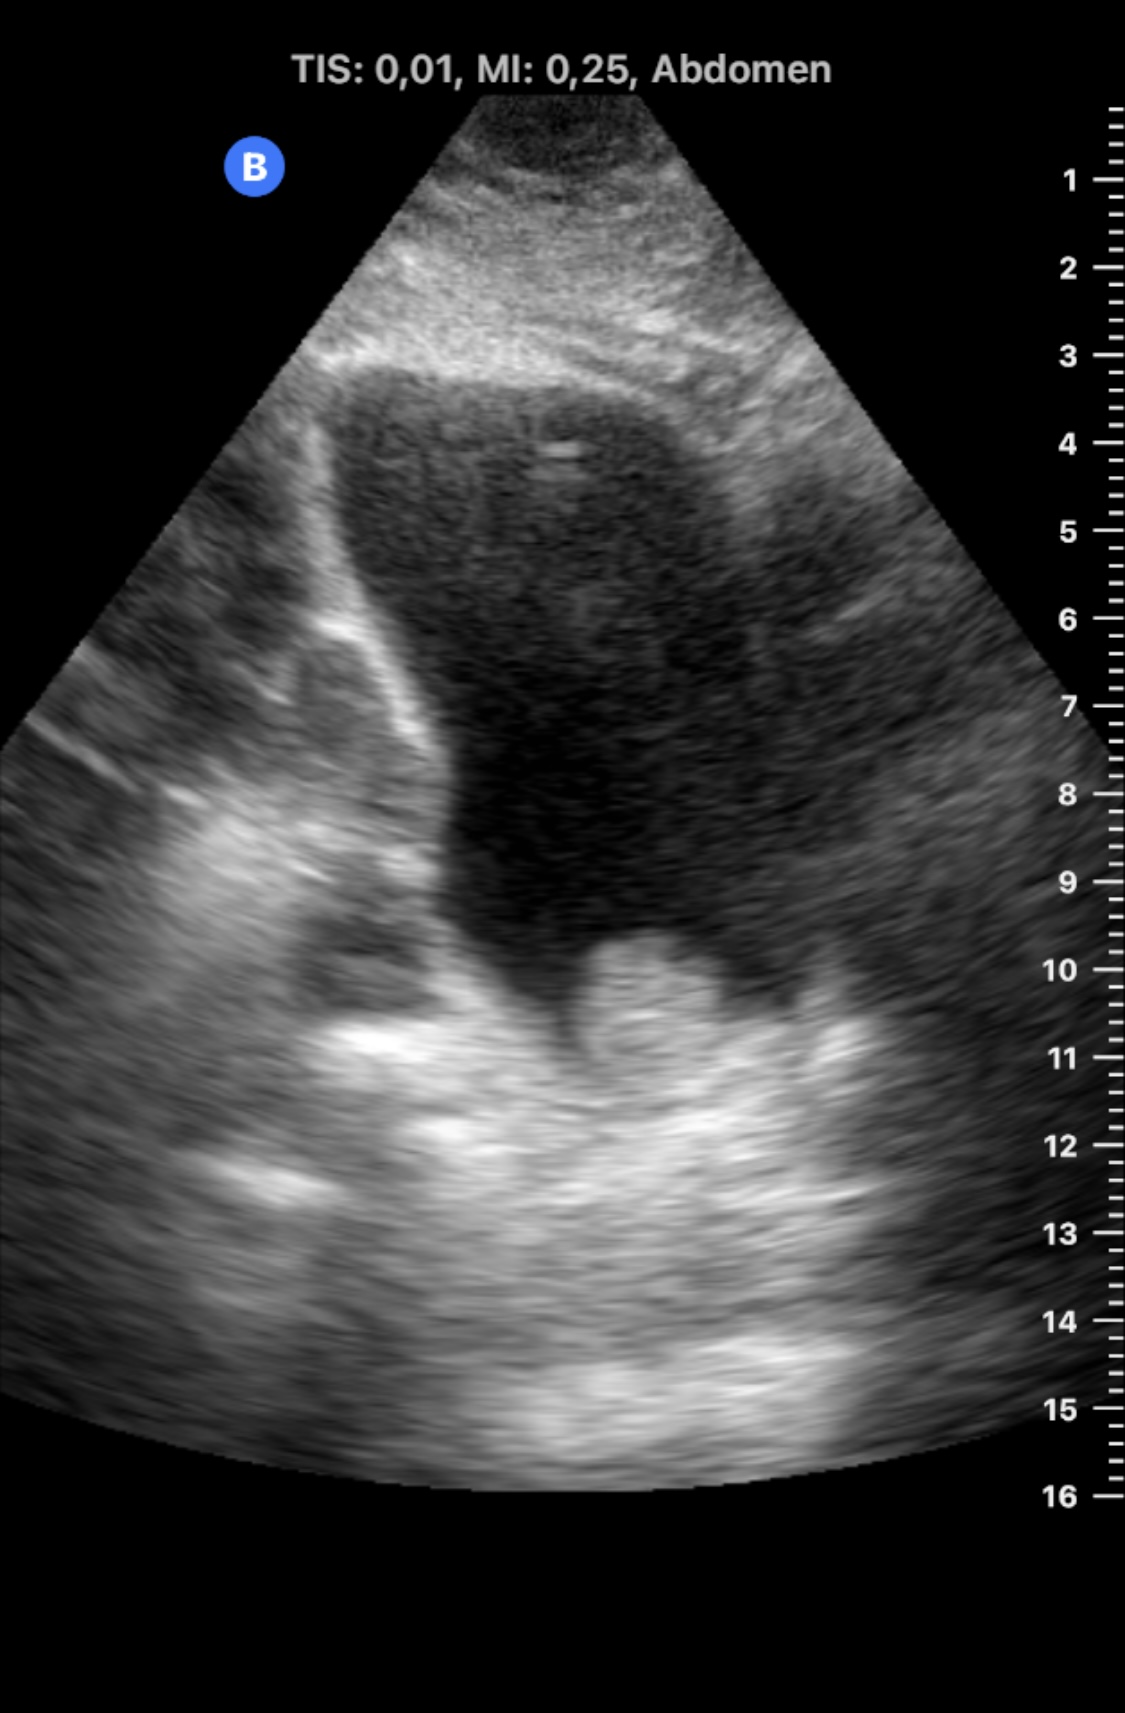

Realizamos Ecografía clínica en consultorio rural, con sonda portátil: riñones con ecoestructura, tamaño y localización normales. Ausencia de dilatación de vías urinarias. Vejiga bien repleccionada en la que se objserva en la base izquierda de la vejiga una imagen homogénea, sólida, intravesica y dependiente de la mucosa, sin sombra acústica posterior. No se modifica con el cambio postural de la paciente.

En urgencias se realizó ecografía reglada: «...Vejiga poco replecionada, poco valorable en este estado, observándose en su margen inferior izquierdo, lo que parece corresponder con una lesión de partes blandas de unos 27,5 x 14 x 26,2 mm y márgenes lobulados, que no se modifica con los cambios posturales».